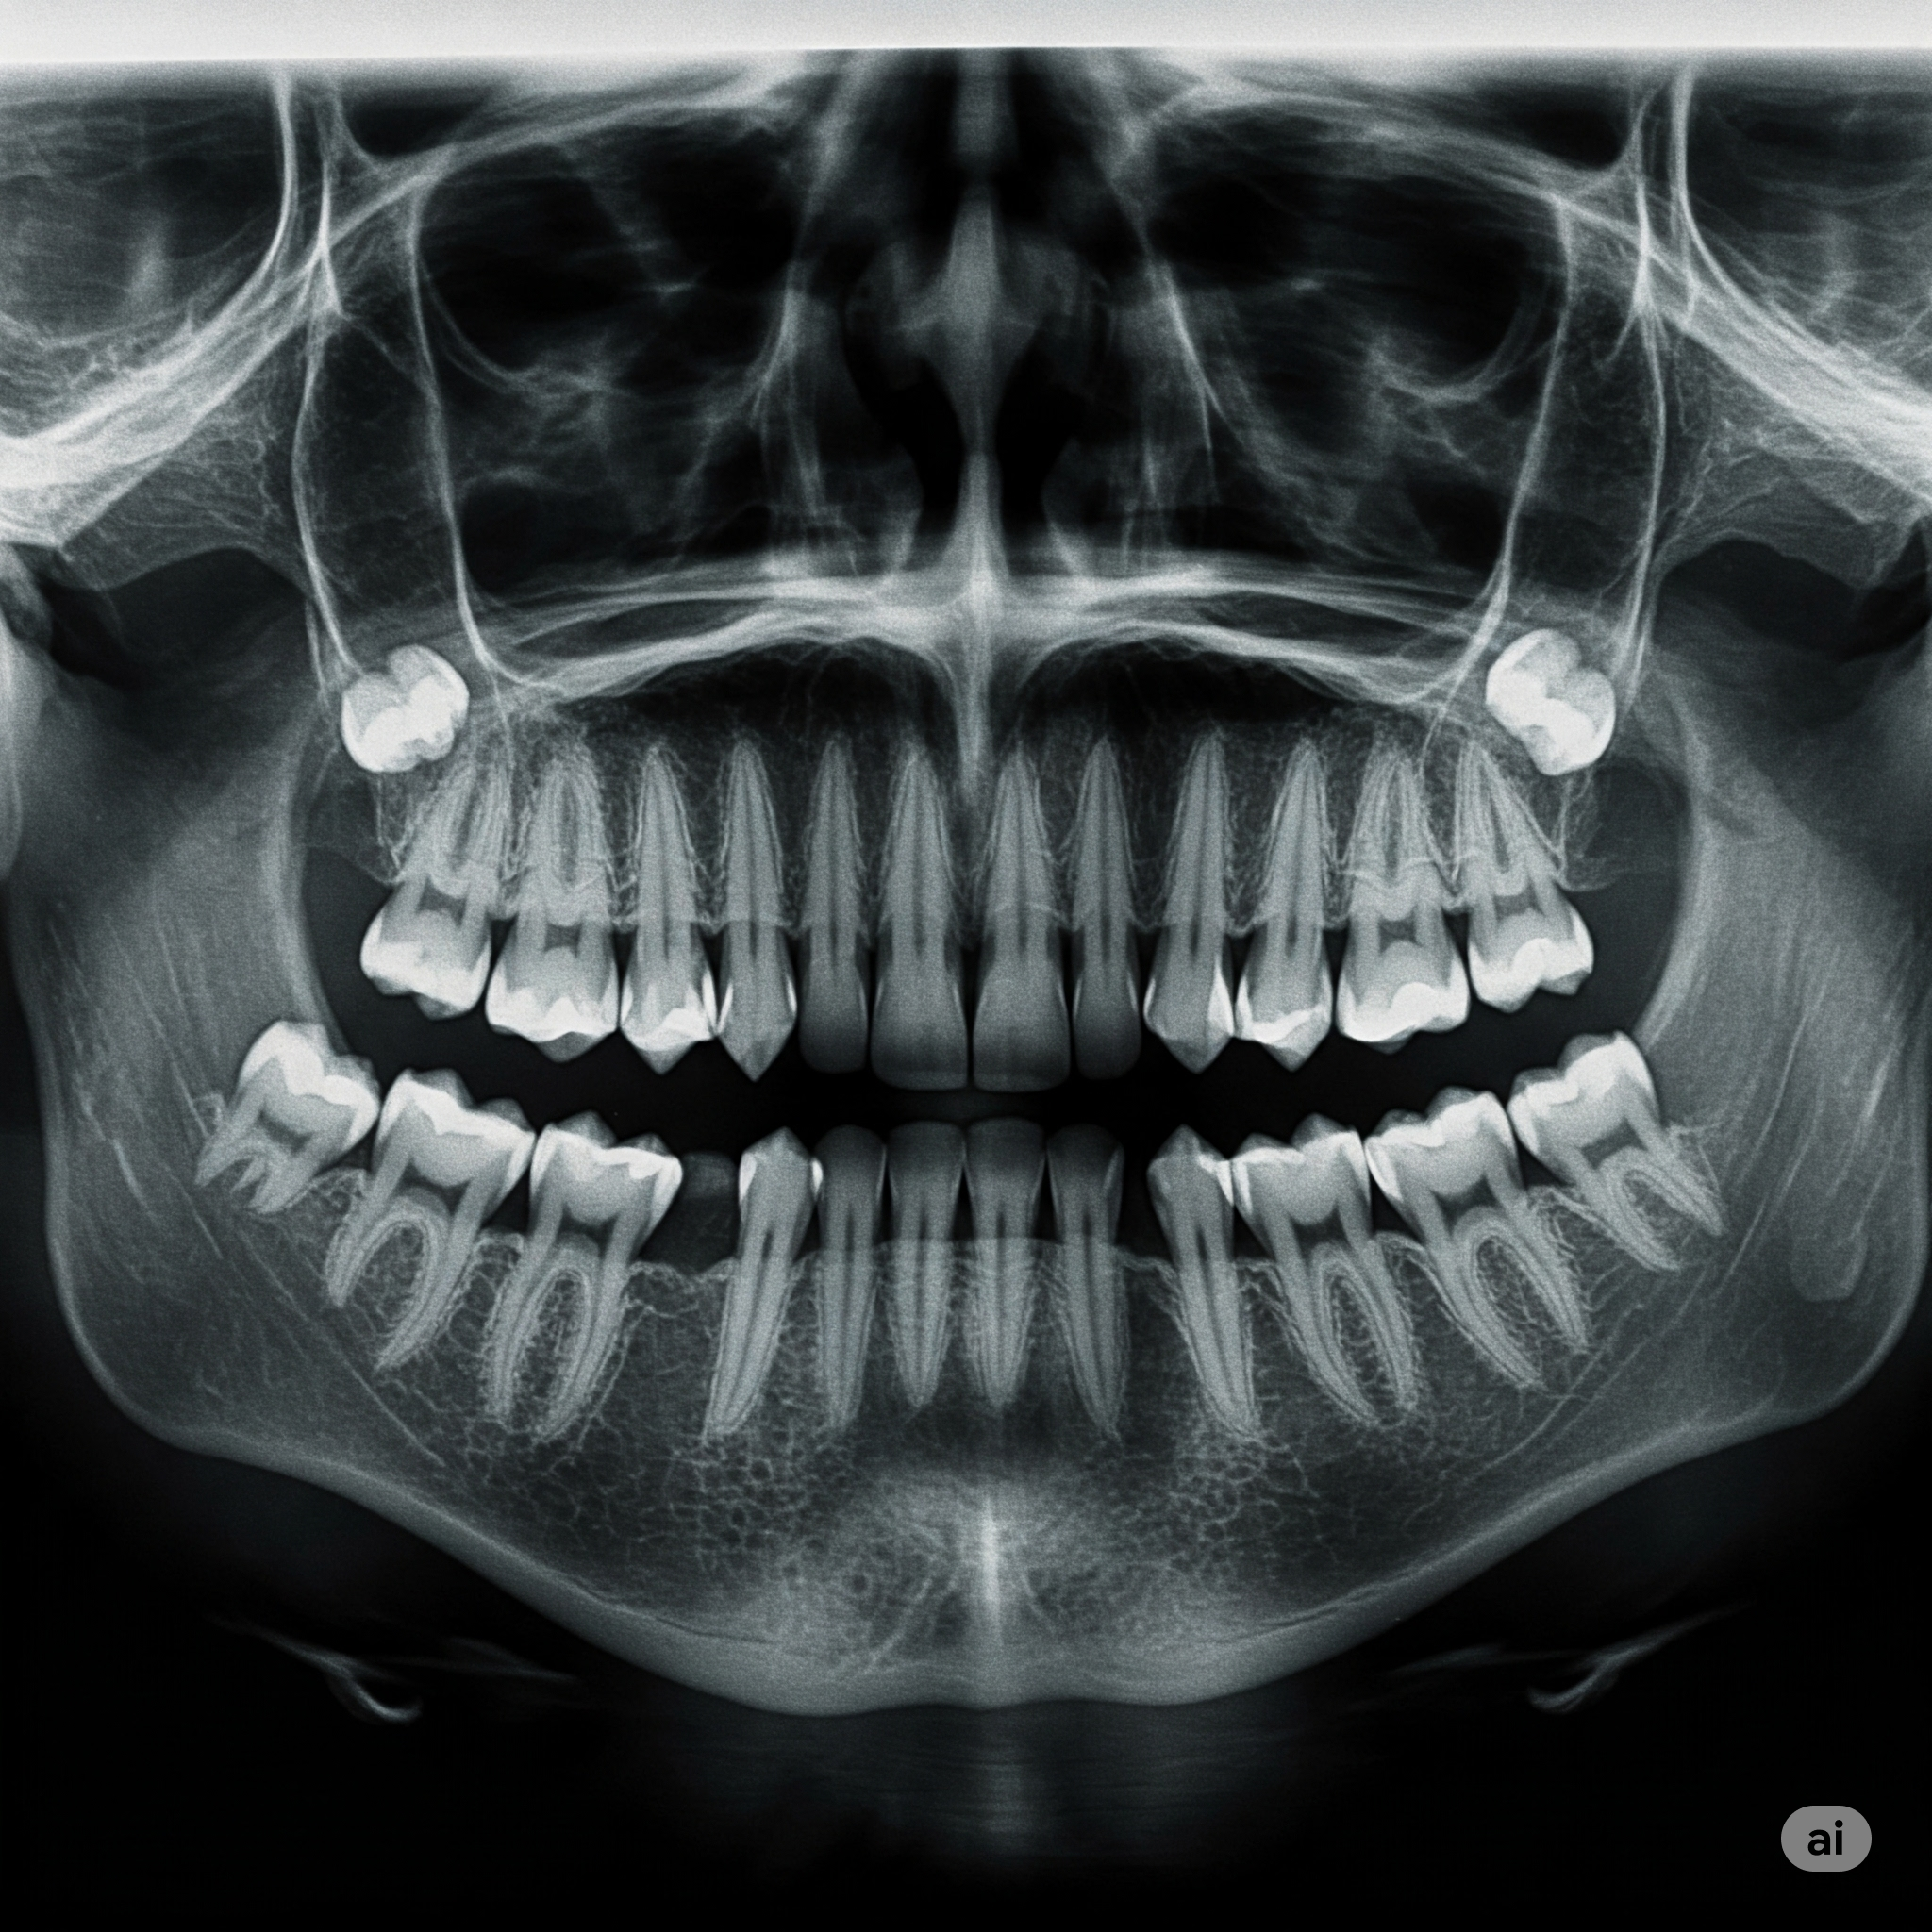

Geleneksel implant uygulamalarında hekimin tecrübesi ve röntgen görüntülerine dayanarak yapılan planlama, cerrahi şablon teknolojisi ile çok daha ileri bir boyuta taşınıyor. Tedaviye başlamadan önce hastanın ağız yapısının detaylı 3 boyutlu görüntülemesi (genellikle Dental Tomografi ile) alınır. Bu görüntüler üzerinde özel yazılımlar aracılığıyla implantın yerleştirileceği ideal konum, açı ve derinlik bilgisayar ortamında hassas bir şekilde belirlenir.

- Detaylı Muayene ve Görüntüleme: Hastanın genel sağlık durumu, ağız içi muayenesi yapılır ve Dental Tomografi (CBCT) alınır.

- Dijital Planlama: Alınan tomografi görüntüleri özel yazılımlara aktarılarak kemik yapısı, sinirlerin konumu ve diğer anatomik detaylar incelenir. İmplantın ideal yeri, açısı ve boyutu dijital ortamda belirlenir. Aynı zamanda protetik (diş üstü) planlama da bu aşamada yapılır.